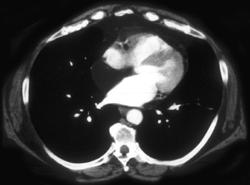

Lymphangetic Spread Due to Cancer